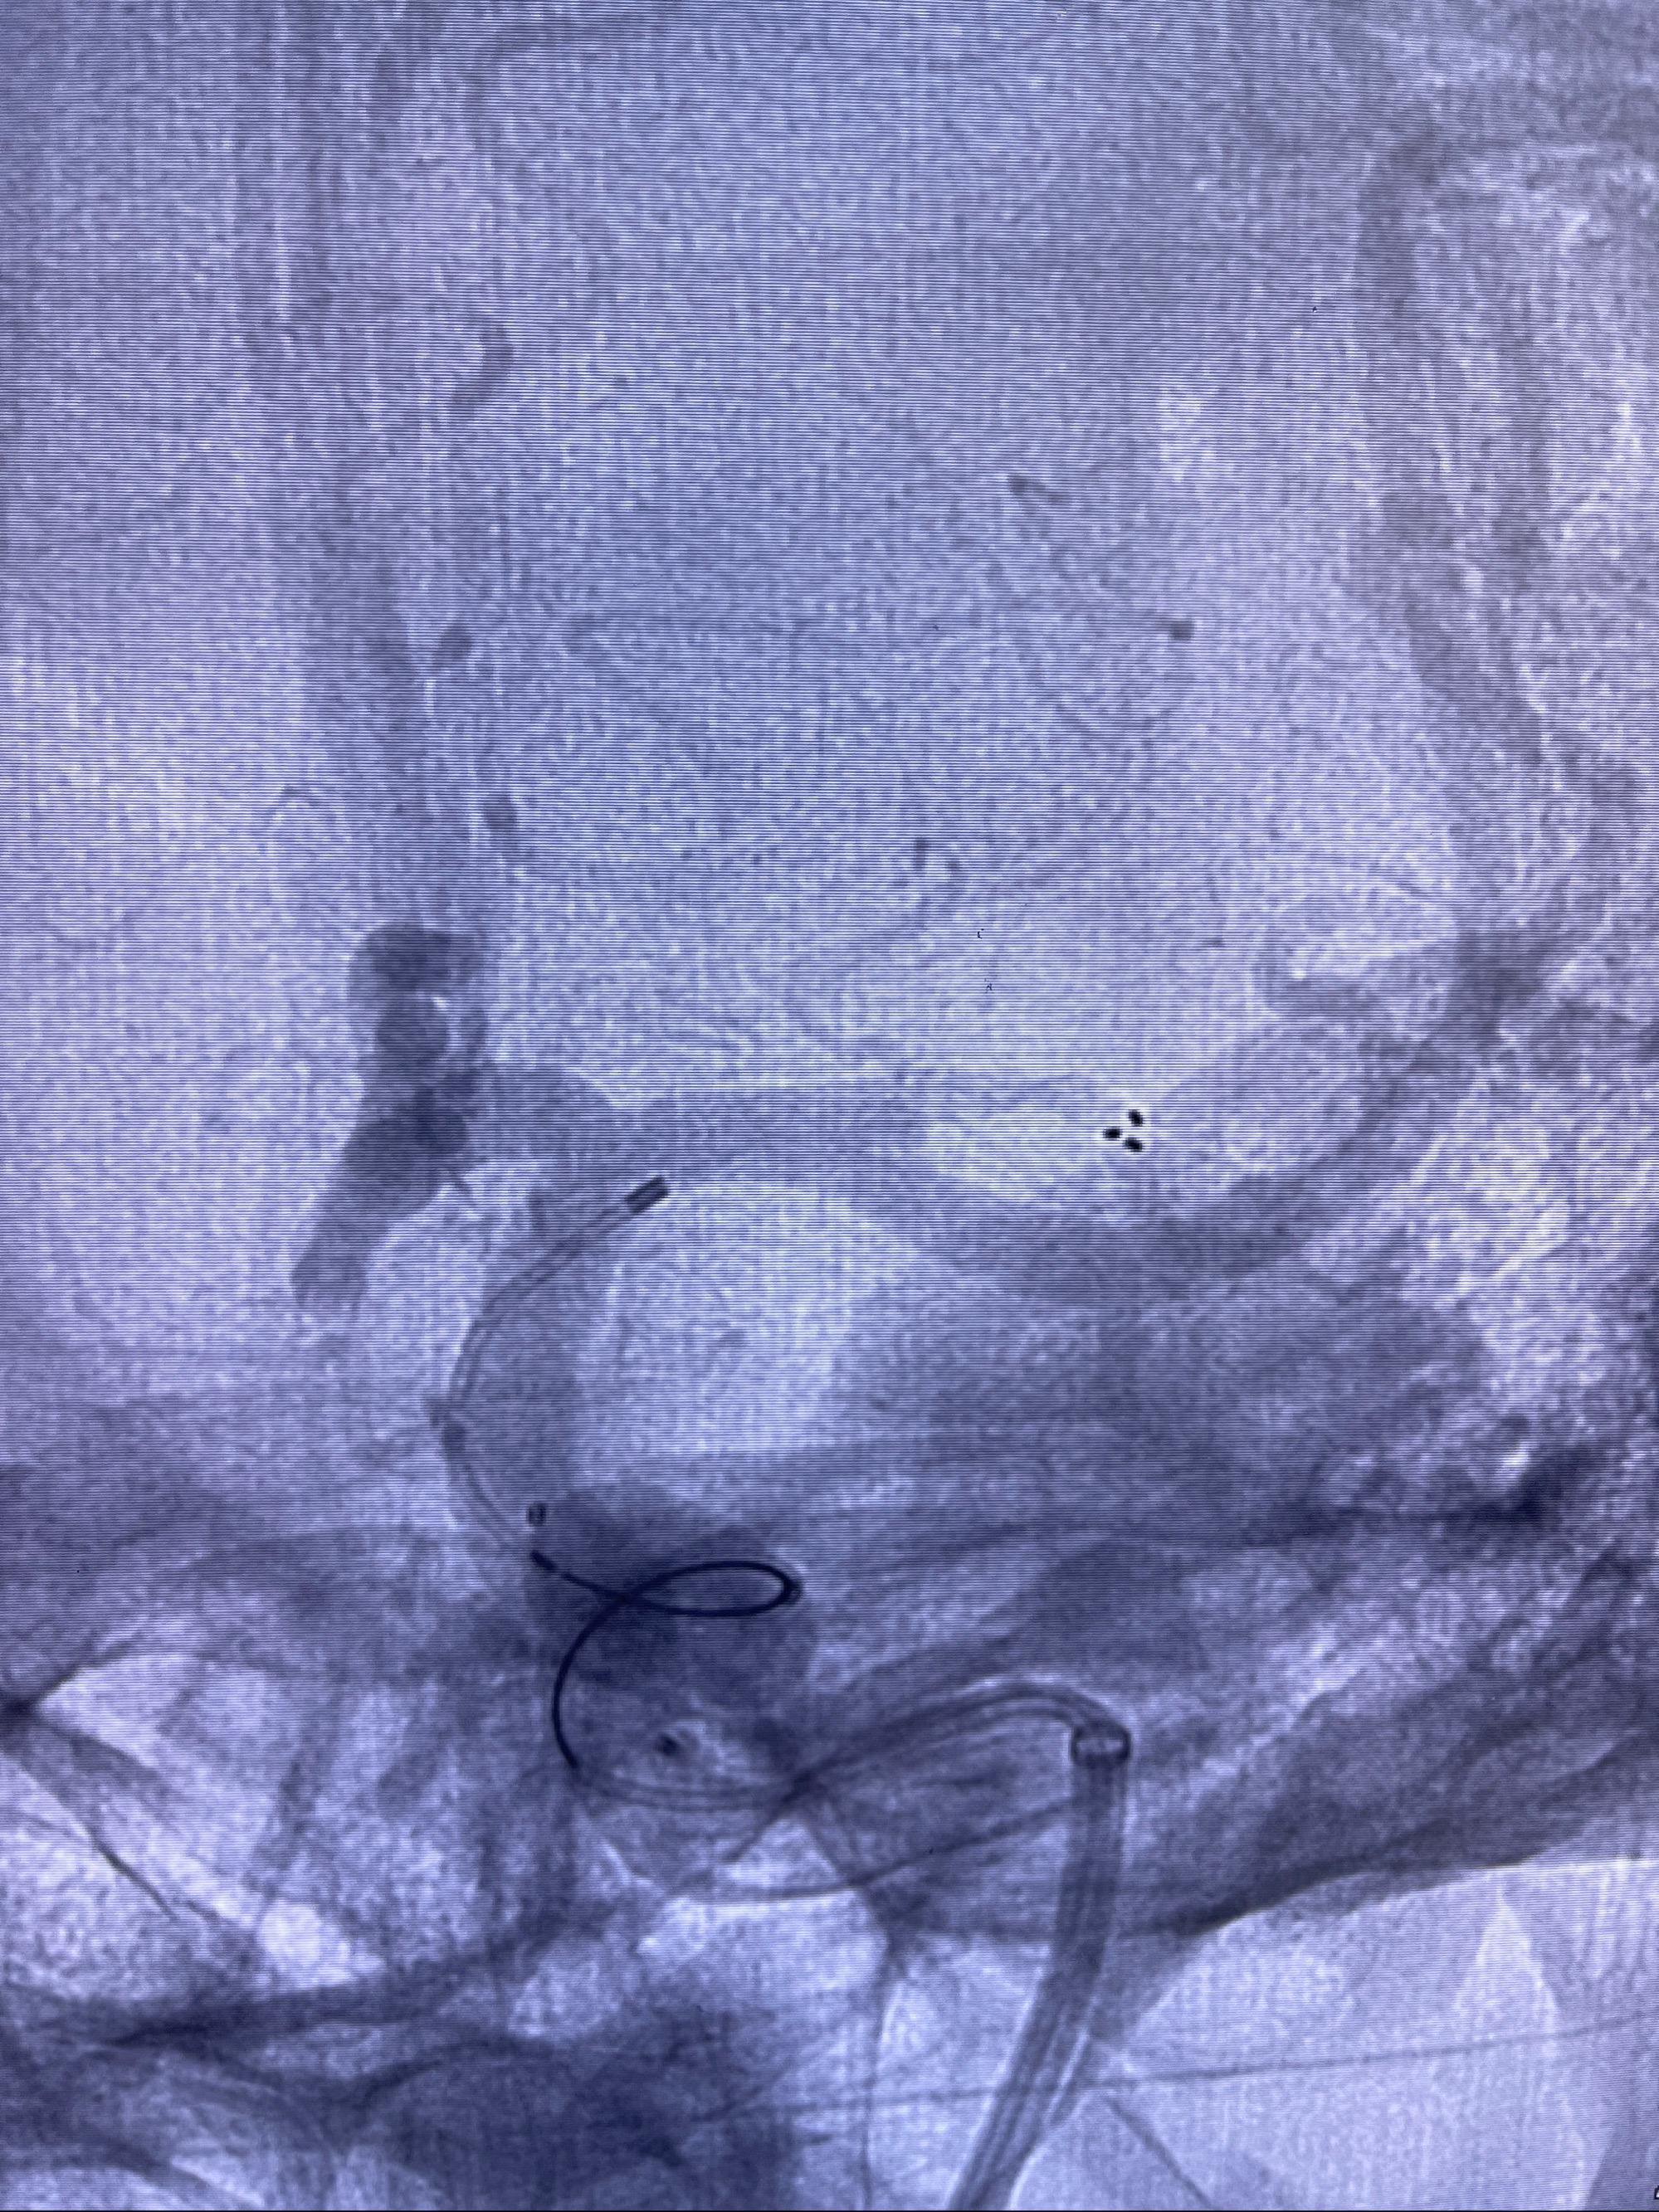

麻醉苏醒佳,遵嘱动作

术后即刻CT